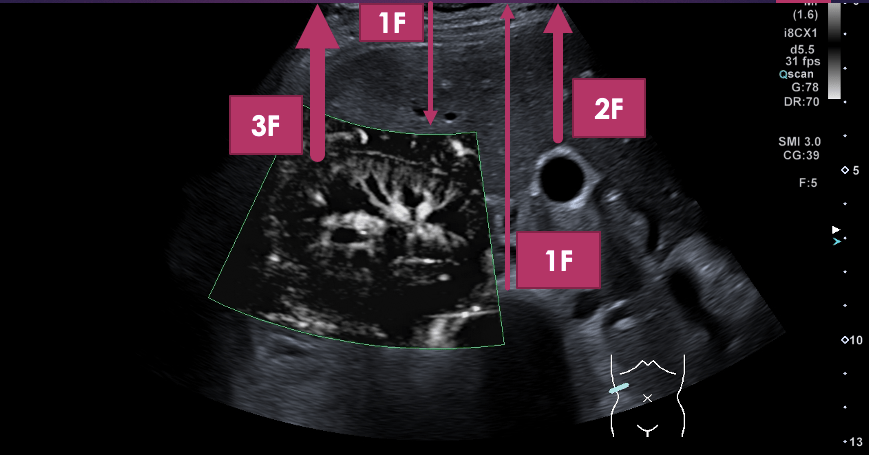

Técnica de Exploración del Labrum Anterior

La exploración comienza colocando el transductor en la posición adecuada para visualizar el tendón del subescapular, similar a la técnica utilizada en sedestación. Luego, se realiza un movimiento pasivo del brazo del paciente, quien debe mantenerlo en flexión y abducción de aproximadamente 90 grados. El operador manipula el brazo para encontrar la mejor visualización del labrum anterior, situado en una posición más profunda.

Valoración de la Articulación Gleno Humeral y la Cápsula Articular Anterior

Además del labrum anterior, esta técnica también permite una evaluación detallada de la articulación gleno humeral y la cápsula articular anterior. Estas observaciones son esenciales para un diagnóstico completo, ofreciendo una comprensión integral de la articulación del hombro.